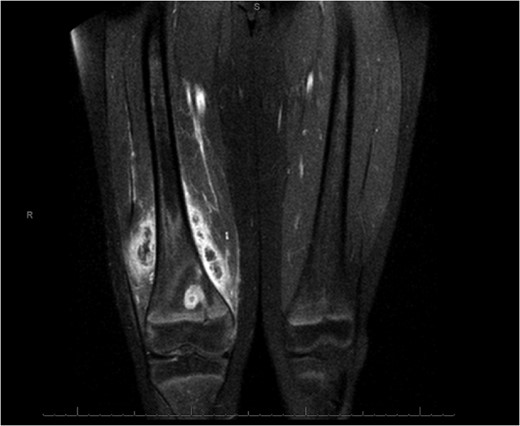

An X-ray, magnetic resonance imaging (MRI) and ultrasound scan was conducted (Fig 1, 2).

MRI Images on admission to Hospital. MRI images displaying ‘osteomyelitis with sequestration and erosion through the posterior cortex, extensively extending into the surrounding soft tissues’.

‘A large complex loculated abscess, 10 cm × 8 × 8 cm, extending between the muscles and extended to the posterolateral aspect of the distal femur. A cloaca is present in the cortical bone on the posterior aspect of the distal femur.’

Coronal slice images of presenting MRI, displaying the brodie's abscess and collection.